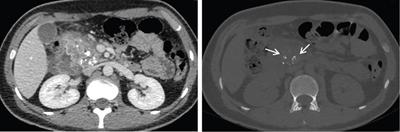

Image

Axial CT image shows pancreatic tissue (arrows) completely encircling the second part of the duodenum in patient with extramural annular pancreas.